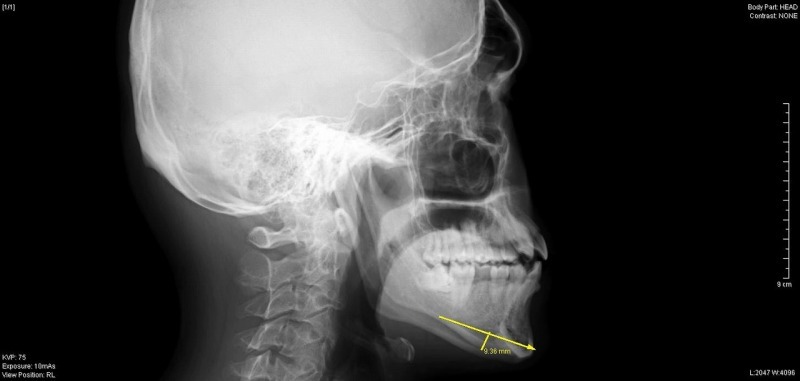

今回は年末に行った、オトガイ形成(顎の骨切り)

について取り上げます。

患者様は、20代 男性で、

顎を短くとがらせたいとの希望でした。

術前のレントゲン検査で最大9mm幅での切除が可能と判断し、

実際も同程度切除が行えました。

通常これぐらい骨切りを行う場合には

顎の中抜き手術を選択される先生が多いのですが、

こちらの手術は、ワイヤー等の異物を残さないため、

レントゲンを撮影する機会の多い歯科治療を受ける際も安心です。